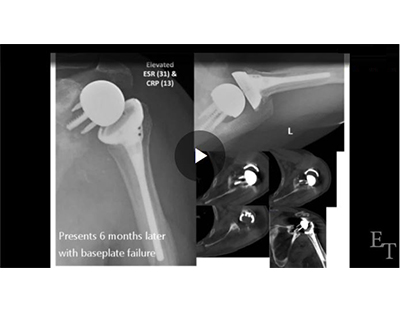

Use of a Functional Antibiotic Spacer for Infected Reverse Shoulder Arthroplasty